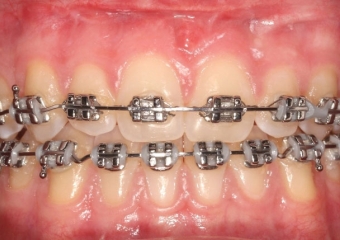

Mordida após a cirurgia realizada em 2016 - Clínica Cliniface

Mordida após a cirurgia realizada em 2016